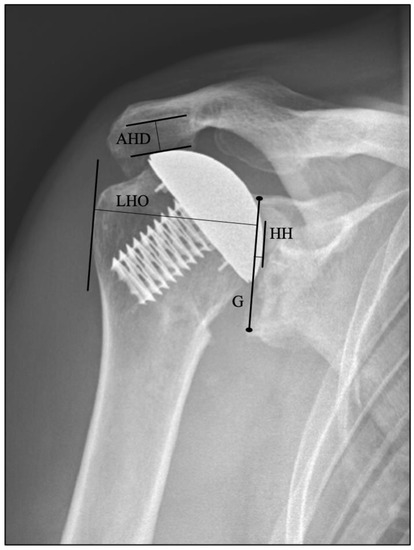

2.4. Clinical and Radiological Evaluations

- Durchholz, H.; Salomonsson, B.; Moroder, P.; Lambert, S.; Page, R.; Audigé, L. Core Set of Radiographic Parameters for Shoulder Arthroplasty Monitoring: Criteria Defined by an International Delphi Consensus Process. JB JS Open Access 2019, 4, e0025. [Google Scholar] [CrossRef]

- Kolk, A.; Overbeek, C.L.; de Groot, J.H.; Nelissen, R.; Nagels, J. Reliability and discriminative accuracy of 5 measures for craniocaudal humeral position: An assessment on conventional radiographs. JSES Int. 2020, 4, 189–196. [Google Scholar] [CrossRef] [PubMed]

- Kadum, B.; Sayed-Noor, A.S.; Perisynakis, N.; Baea, S.; Sjoden, G.O. Radiologic assessment of glenohumeral relationship: Reliability and reproducibility of lateral humeral offset. Surg. Radiol. Anat. 2015, 37, 363–368. [Google Scholar] [CrossRef]